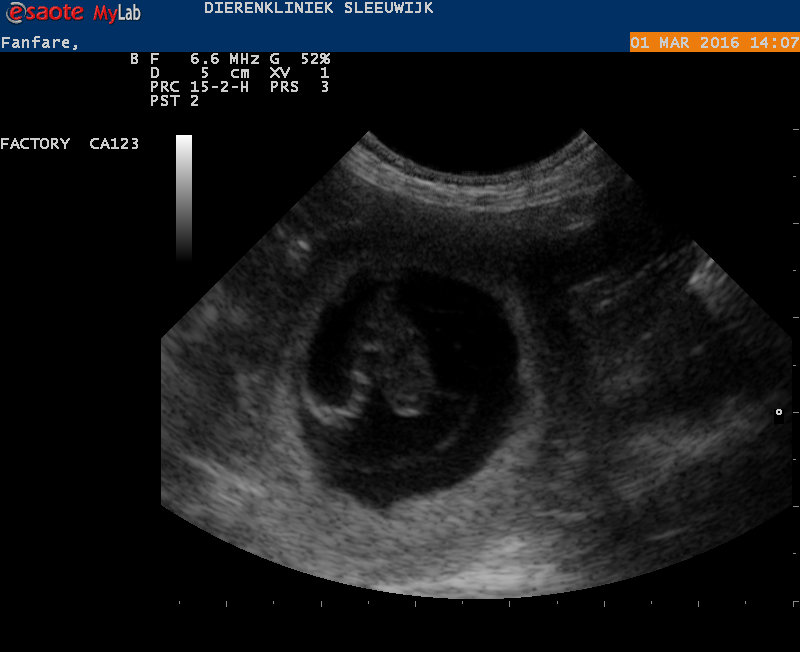

Fanfare is drachtig

Vandaag een echo genomen. We zagen 8 vruchtjes. Onze vrolijke Fanfare stond kwispelend voor de echo.

Een van de vruchtjes